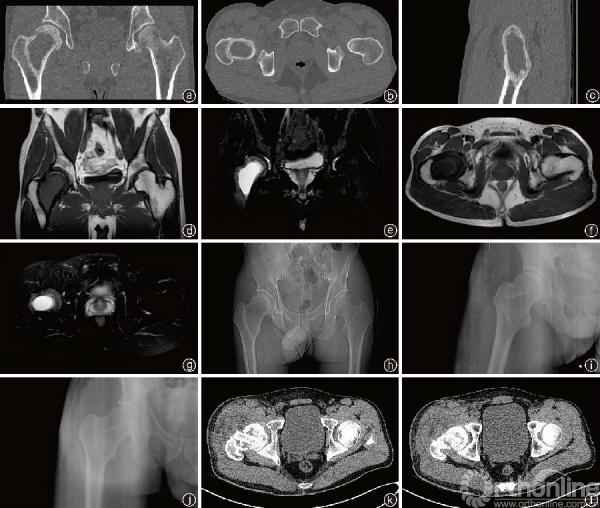

影像学资料a~c:术前额状位、冠状位、矢状位CT片示右侧股骨颈椭圆形溶骨性破坏区,骨皮质变薄,连续性尚存在;

d~g:术前MRI额状位、冠状位的T1、T2像示右侧股骨近段囊状长T1长T2信号影,范围约43 mm×29 mm×66 mm,边界欠清,其内尚均匀,边缘见稍低信号环,波及股骨头、股骨颈及转子间,周围软组织信号均匀,未见异常;

h:术前骨盆X线片见右侧股骨颈囊性病变;

i:术后复查右股骨近端正位X线片,可见植骨块及颗粒松质骨填充良好;

j:术后半年复查X线片见骨质基本愈合;

k:术后3d复查CT可见植骨块及填塞颗粒松质骨;

l:术后3个月复查CT见出现骨性愈合